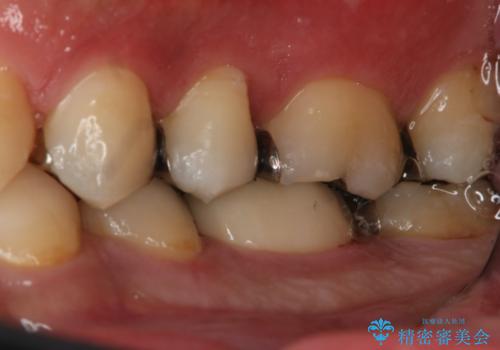

- 左下6番の銀歯が不適であったためやり変えを勧めたところセラミックでの治療を希望された患者様です。

切削量などを考慮し、フルジルコニアクラウンでの治療を選択しました。

う蝕が深く切削量が多くなりましたが痛みなどは起きなかったので、予定通りフルジルコニアクラウンでの治療で進めました。